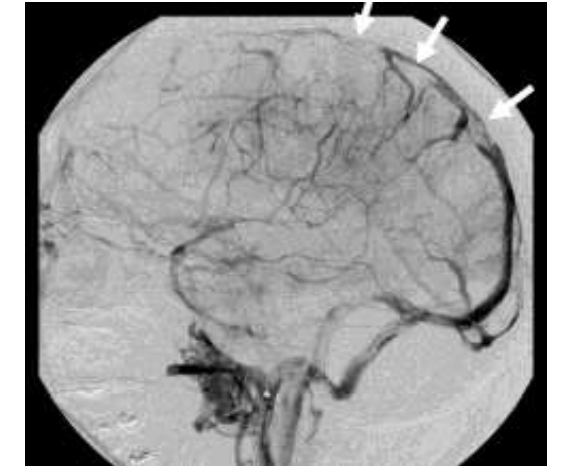

• Chụp động mạch não số hóa xóa nền đặc hiệu hơn cắt lớp vi tính tĩnh mạch não hay cộng hưởng từ tĩnh mạch não nhưng thường không cần thiết. Chỉ định khi chụp cắt lớp vi tính hay cộng hưởng từ nghi ngờ hoặc không xác định được chẩn đoán.

• Trên phim chụp động mạch não số hóa xóa nền thấy sự kết thúc đột ngột của tĩnh mạch vỏ não được bao quanh bởi các "tĩnh mạch nút chai" giãn và ngoằn ngoèo.

• Hình ảnh điển hình khác có thể không thấy được toàn bộ hoặc một phần của xoang tĩnh mạch, thoát máu chậm kèm theo đảo ngược dòng chảy trong tĩnh mạch.

Hình 4: Hình ảnh huyết khối xoang dọc trên trên phim chụp DSA ở người bệnh tại Bệnh viện Bạch Mai